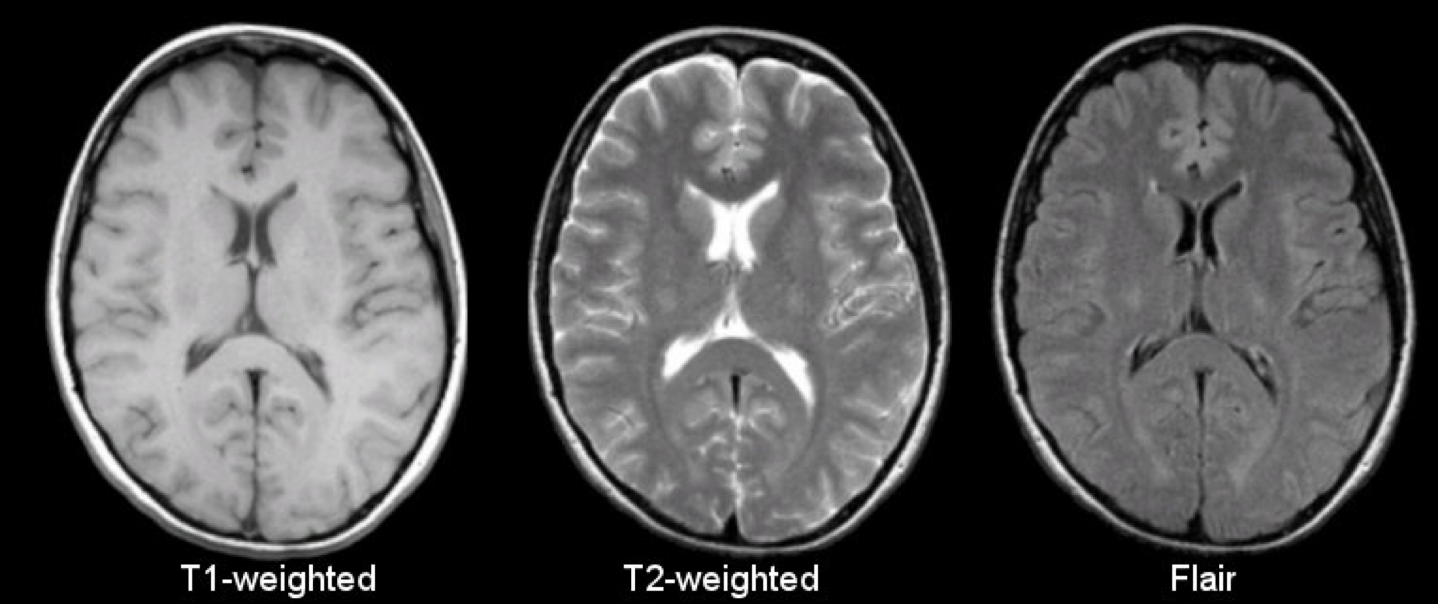

| Sequences | Hyperintense | Hypointense |

|---|---|---|

| T1-weighted | Fat, adipose tissue (white brain matter) Contrast media | Water (CSF, edema ) Bone Ligaments, tendons Air (no signal) |

| T2-weighted | Water (CSF, edema ) Fat (less hyperintense than in T1) | Bones Ligaments, tendons Air (no sign |